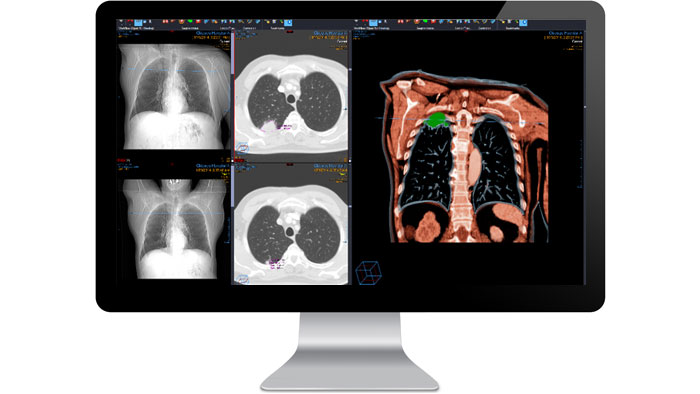

PowerViewer

Speed interpretation with multiplanar reconstruction, vascular representation and volume rendering at one click of the mouse. The volumetric PowerViewer enhances the traditional two-dimensional viewer and creates a single, virtual study with real-time 3D volumetric registration of all relevant studies, including priors, with synchronized views across multiple data sets.

Advanced 3D imaging

Create, modify and view 3D images without leaving the source data. Vue PACS 3D imaging efficiently handles huge data sets, providing remarkable speed and simplicity for displaying current and prior studies side by side and applying 3D tools to both. 3D analysis options include maximum intensity projection (MIP), volume rendering and tissue definition. 2D and 3D-rendered images are automatically loaded to provide a summary of the entire anatomy, with automatic 3D positioning of cross-referencing lines.